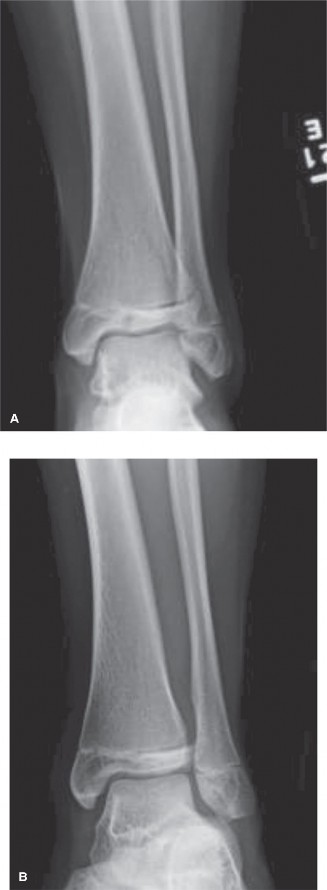

Case Eight Distal Tibial Transitional Fractures

These include the Tillaux fracture (Salter-Harris III of the anterolateral distal tibia) and the Triplane fracture (Salter-Harris IV equivalent occurring in three planes). These occur during the asymmetrical closure of the distal tibial physis (closing central to medial to lateral). Displacement greater than 2 millimeters requires open or arthroscopically assisted reduction and internal fixation to prevent post-traumatic arthritis. Fixation is typically achieved with epiphyseal or metaphyseal parallel cannulated lag screws, ensuring no screws cross the remaining open physis.